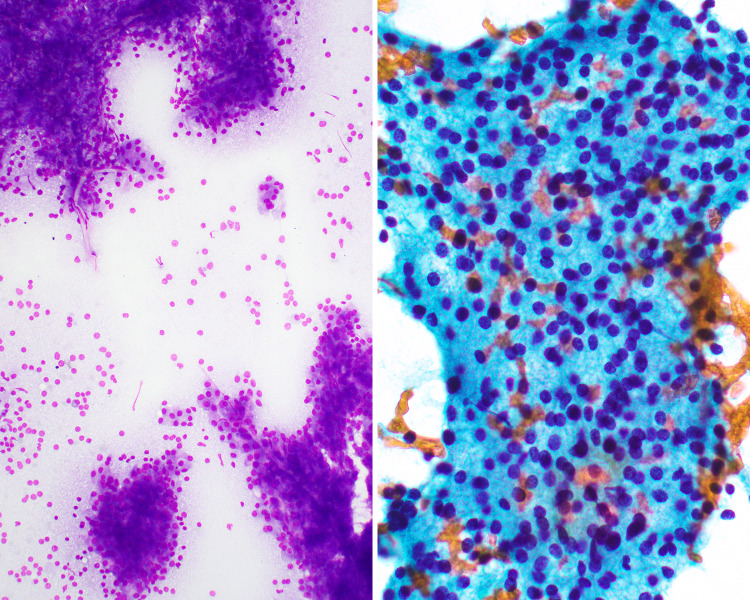

Fig. 15.

FNA showing (left) papillary clusters (Diff Quick stain, magnification × 20) and (right) a sheet of serous acinar cells (Papanicolaou stain, magnification × 40) characteristic of acinic cell carcinoma